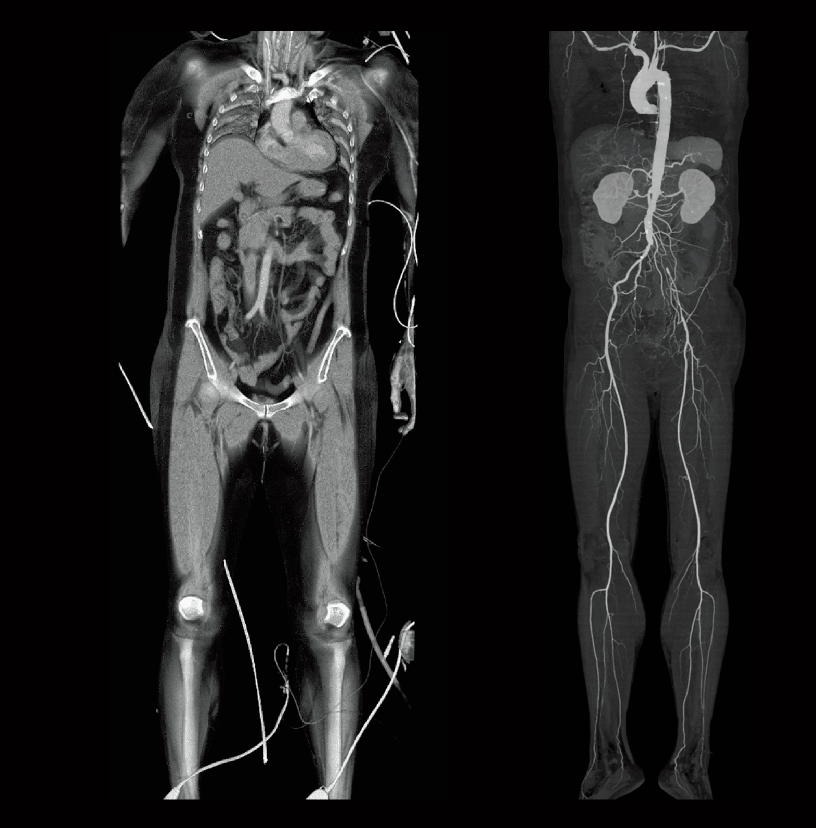

Abdominal aortic occlusion

Intraoperative oxygen desaturation (Left)

Left common iliac artery occlusion (Right)

- * Images other than the axial image were processed by the 3D image analysis system SYNAPSE 3D.